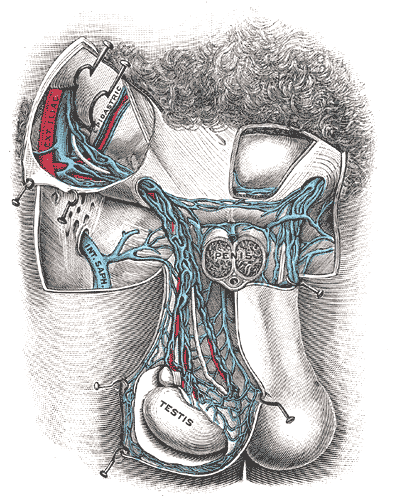

Varicocele is the dilation of the spermatic vein because of impaired drainage.

Varicocele presents as a “bag of worms” like scrotal enlargement.

Varicoceles are typically left sided.

The left testicular vein drains into the left renal vein.